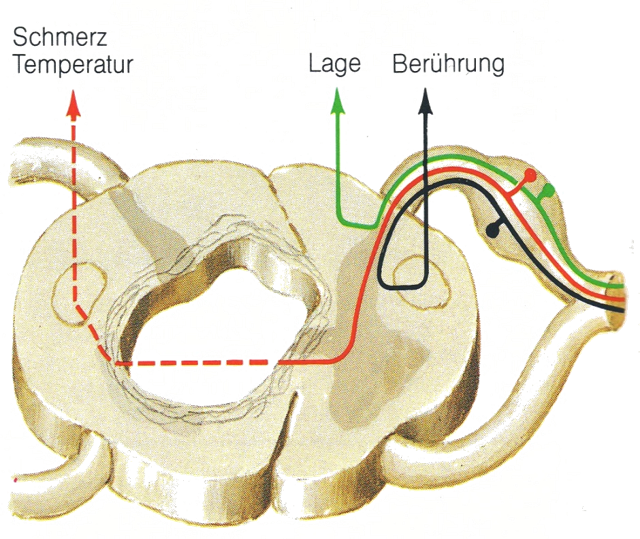

Die Symptomatik der Syringomyelie ist vielfältig. Meist fällt die Krankheit zuerst durch Schmerzen/Kribbeln/Taubheitsgefühl im Bereich der Schultern und der Arme auf. Bei fortschreitender Erkrankung kommt es durch Schädigung der Leitungsbahnen für die Temperatur- und Schmerzempfindung zu Verletzungen und Verbrennungen, die der Patient selbst nicht fühlt. Auch die anderen Qualitäten der Sensibilität, wie die Berührungsempfindlichkeit oder die Tiefensensibilität (die anzeigt, in welcher Stellung sich der Körper oder die Gelenke befinden), können ein- oder beidseitig an Armen oder/und an den Beinen gestört sein. Störungen der Blasen- und Darmentleerung und sexuelle Funktionsstörungen sind ebenfalls möglich. Auch die Muskelaktivität kann gestört sein. Es kann zu Lähmungen oder spastischen Veränderungen, vornehmlich der oberen, aber auch der unteren Extremität kommen.